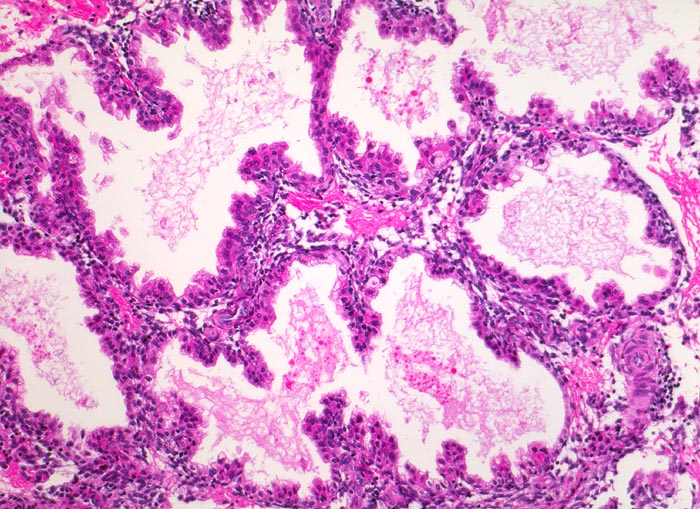

Abortkurettage: Schwangerschaftsendometrium

Das Schwangerschaftsendometrium besteht aus stark proliferierten hypersekretorischen ausgeweiteten Drüsen. Das Drüsenepithel bildet papilläre und pseudopapilläre in die Drüsenlumina hineinragende Proliferate. Die Zellkerne des Drüsenepithels sind hyperchromatisch und polymorph (sogenanntes Arias Stella Phänomen).

Missed abortion in der 11. Schwangerschaftswoche, sonographisch entsprechend der 9. Schwangerschaftswoche.